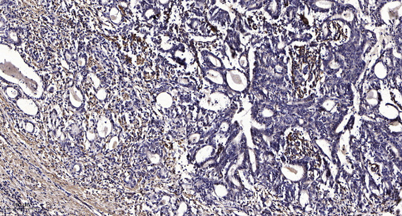

Immunohistochemical analysis of paraffin-embedded human Gastric adenocarcinoma. 1, Antibody was diluted at 1:200(4 overnight). 2, Tris-EDTA,pH9.0 was used for antigen retrieval. 3,Secondary antibody was diluted at 1:200(room temperature, 45min).